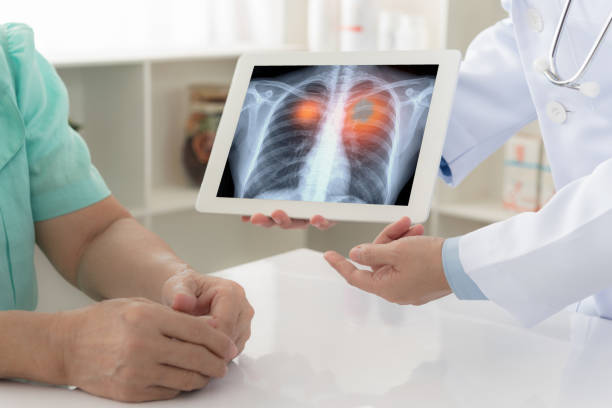

폐암은 초기에는 증상이 미미하거나 없을 수 있습니다. 그러나 조기에 발견하고 진단받으면 치료의 성공률이 훨씬 높아집니다. 초기에 폐암을 발견하면 조기 치료를 시작하여 종양의 성장과 전이를 제한할 수 있습니다. 뿐만 아니라, 치료에 있어 다양한 치료 방법을 활용할 수 있어 폐암 초기 증상을 잘 알고 있는 것이 중요합니다.